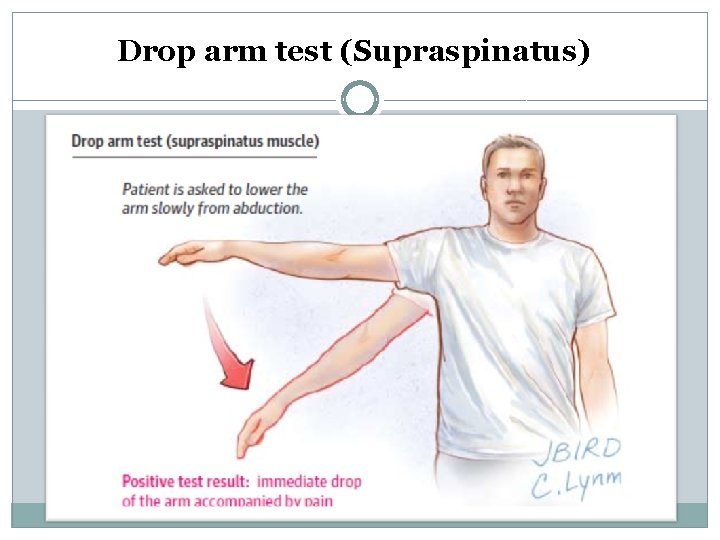

. Clinical sign and symptoms Acute tearing Pain & weakness of abduction and ext-Rotation Chronic tearing Crepitation, stiffness, atrophy and weakness Supraspinatus tearing Inability to abduction, drop arm test Infraspinatus tearing Inability to Ext. Rotation, can't reach spoon to mouth, inability to combing ext- rotation lag test Subscapularis tearing Internal rotation lag test

Drop arm test (Supraspinatus)